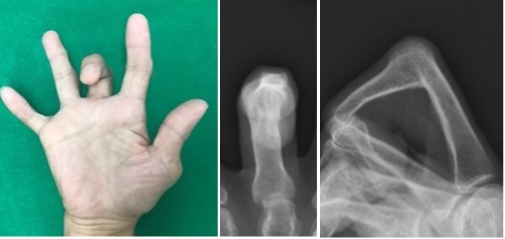

関節リウマチ患者に対する腱移行および手関節形成術

手関節の変形により腱断裂(特に伸筋腱)が生じ、急に指が伸びなくなる患者さんがいます。小指から始まり、比較的早期に手術をしない薬指中指と断裂が進行します。

断裂が進行しないように手関節の形成と、切れた腱に対しては直接縫合することは困難なため、隣接する正常な腱を用いて腱移行や腱移植を行ないます。

術前(写真)

術前(レントゲン)

手術前の指の伸展不足が改善しています